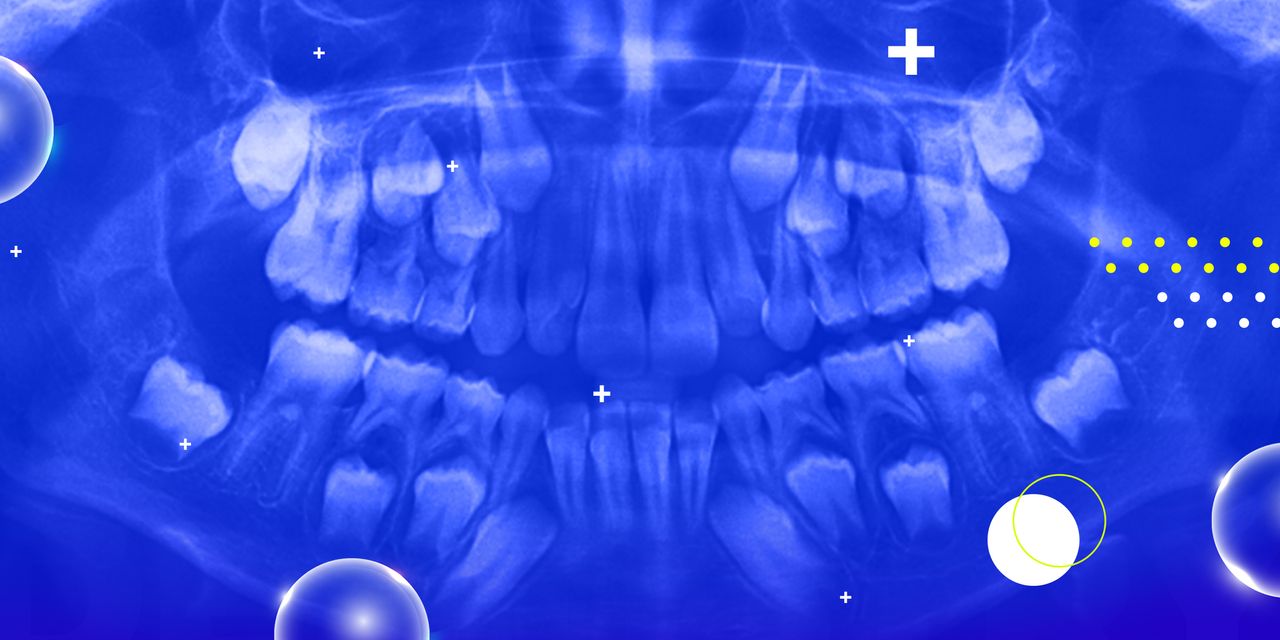

Pediatric Oral Radiology: From Radiation Safety to Lesions and CBCT

This seminar will provide to the attendee the most common radiographic lesions that are presented in infants, children and adolescents. The seminar will use case-presentation as the learning and discussion format and will cover the entire spectrum of oral radiology in pediatric dentistry. Topics such as radiation safety, digital radiology, CBCT in pediatric dentistry, radiographic interpretation and common radiographic lesions in children will be covered in this seminar.

After attending this seminar, the participant will be able to:

– Understand the importance of “building” a differential interpretation in radiology

– Learn the most common radiographic lesions in infants, children and adolescents

– Learn the indications of CBCT within the frame of practicing pediatric dentistry

– Understand the importance of radiation safety in the practice of dentistry with children and adolescents.